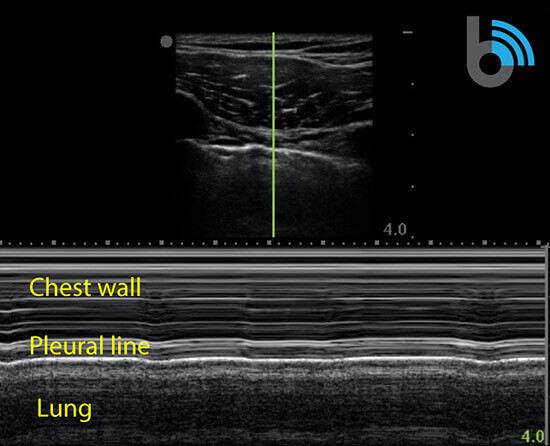

M-mode (motion mode)

- Measures the motion of a structure over a period of time.

- After obtaining a B-mode image, a single scan line (yellow line) is placed over the pleura between the ribs.

- A normal aerated lung will present as the “seashore sign” or “waves on the beach”.

- The “waves” will appear as horizontal, hyperechoic lines.

- Represents the lack of motion in the chest wall.

- The area below the pleural line will appear granular (“beach”)

- Results from the motion of the lung.